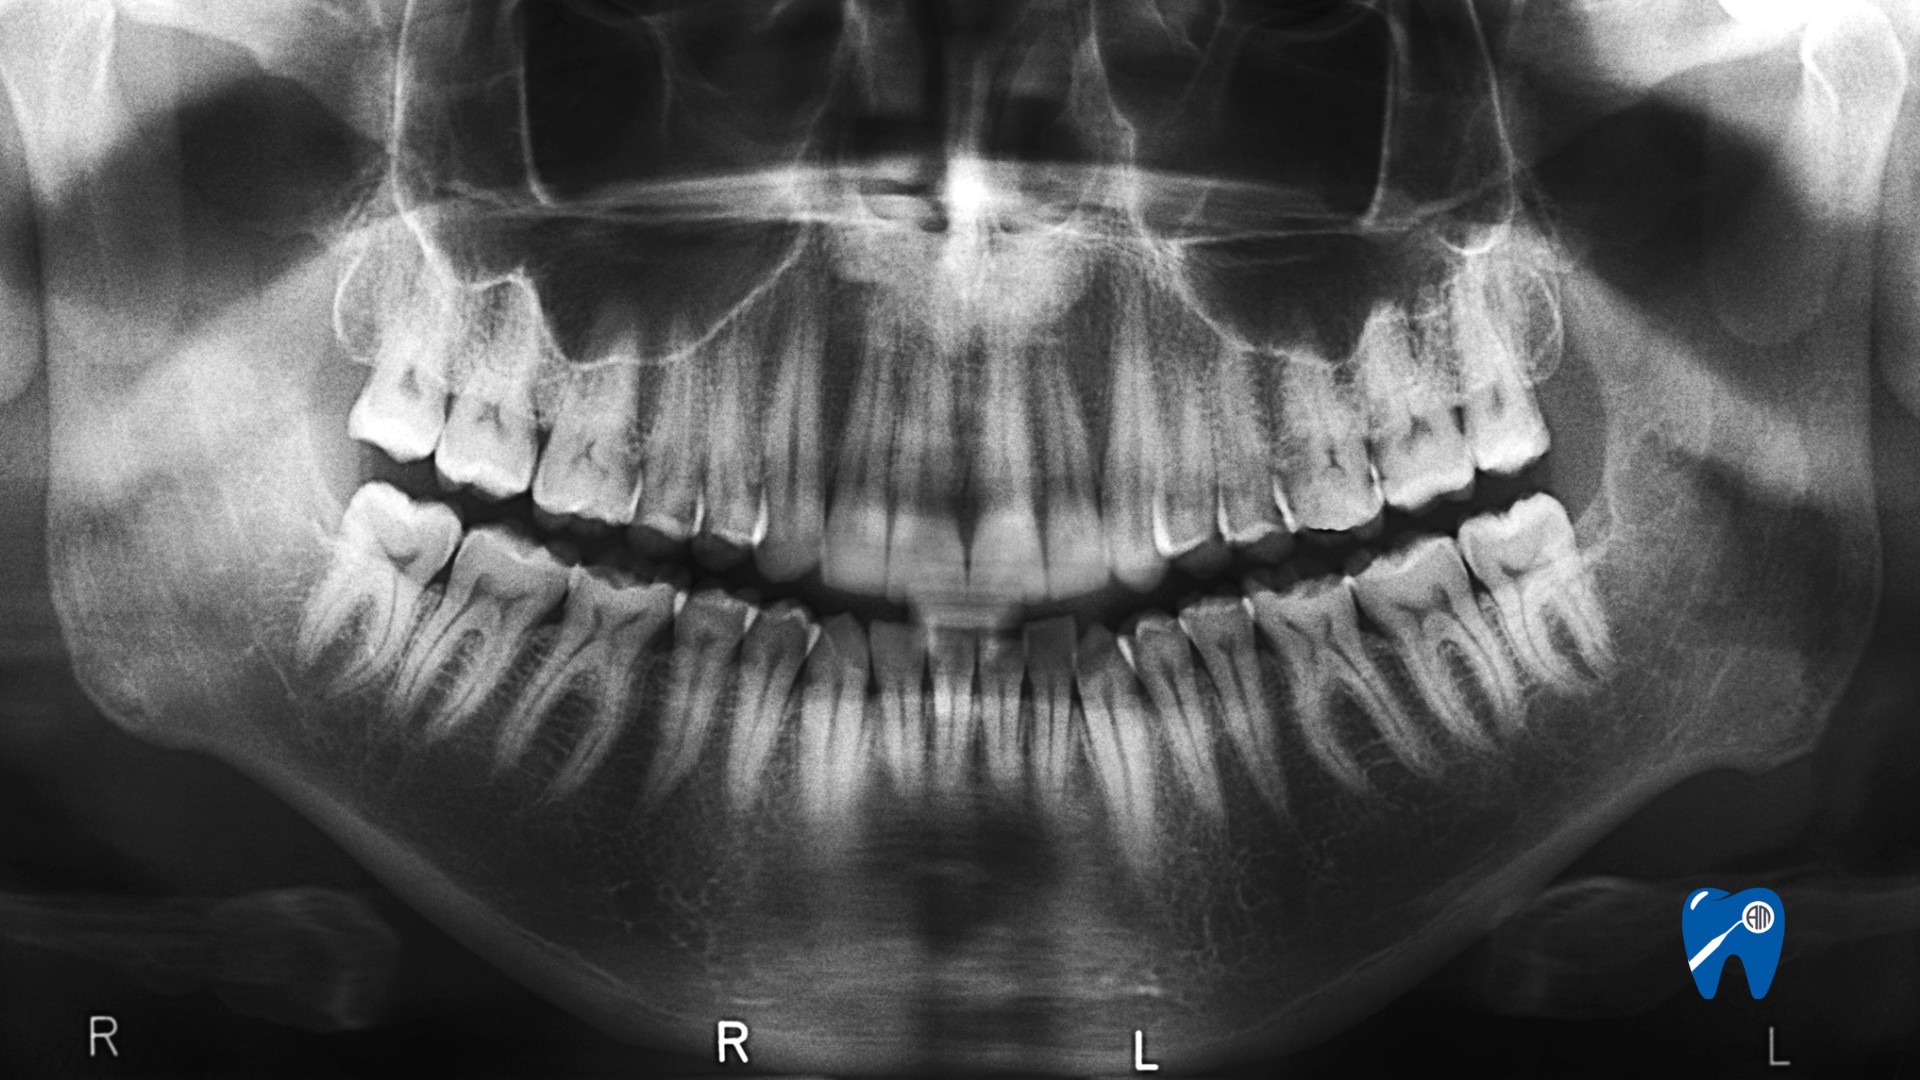

Zdjęcie panoramiczne zębów to jedno z najczęściej wykonywanych badań w diagnostyce stomatologicznej. Pozwala zobaczyć cały układ szczęki i żuchwy, korzenie zębów, zatoki, stawy skroniowo-żuchwowe oraz ewentualne zmiany zapalne. Pacjenci często zwlekają z jego wykonaniem, bo nie czują bólu lub liczą, że problem „sam przejdzie”. Tymczasem wiele schorzeń rozwija się bezobjawowo. Kiedy więc warto zrobić zdjęcie panoramiczne zębów od razu, zamiast czekać, aż ból się nasili?

Zdjęcie panoramiczne zębów, czyli pantomogram (OPG), pozwala lekarzowi ocenić stan całego uzębienia i okolicznych tkanek twardych. To badanie zlecane nie tylko wtedy, gdy boli, ale także profilaktycznie – raz na 2 lata. Najczęstsze wskazania to planowanie usunięcia ósemek, zwłaszcza zatrzymanych lub wyrzynających się w sposób nieprawidłowy. Dzięki OPG lekarz dentysta może dokładnie zobaczyć, jak blisko korzenie ósemek znajdują się nerwu żuchwowego i zaplanować bezpieczne usunięcie z minimalnym ryzykiem powikłań.

Zdjęcie panoramiczne zębów jest też konieczne przy planowaniu implantów. Umożliwia ocenę ilości i jakości kości, położenie zatok szczękowych i sąsiednich struktur. Pomaga też przy przewlekłym bólu, gdy trudno wskazać źródło – na przykład w sytuacji, gdy pacjent odczuwa dyskomfort, ale punktowe RTG nie pokazuje przyczyny. Wtedy pantomogram ujawnia zmiany okołowierzchołkowe, torbiele lub zęby zatrzymane.

Choć zdjęcie panoramiczne zębów daje bardzo szeroki obraz jamy ustnej, ma swoje ograniczenia. Pantomogram jest obrazem dwuwymiarowym, więc nie pokazuje głębokości struktur i może nie oddawać rzeczywistych odległości. W takich sytuacjach lekarz może zalecić CBCT (tomografię stożkową), która daje trójwymiarowy, przestrzenny obraz i pozwala precyzyjnie ocenić np. przebieg kanałów korzeniowych, położenie implantu czy zatoki szczękowe.